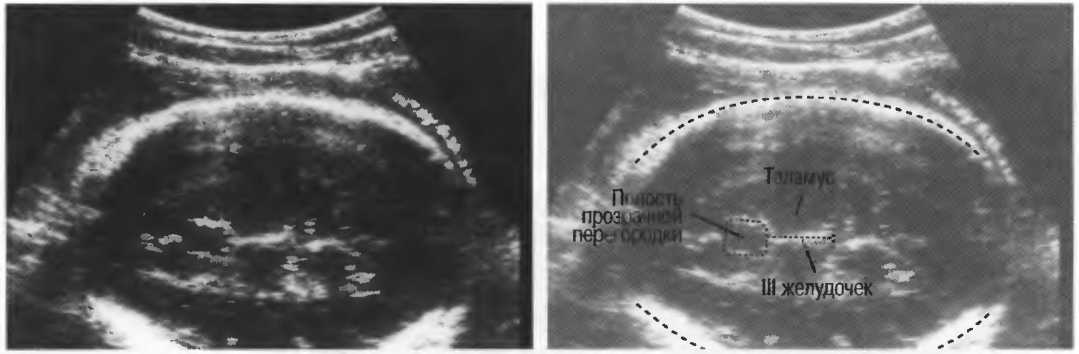

- При удовлетворительном качестве изображения можно получить изображение полости прозрачной перегородки головного мозга у 35-недельного плода (рис. 23). Этот тест можно использовать для контроля качества в случаях, когда нет фантома. Данный тест необходимо проводить каждые 3 мес.

Рис.23а. На любом приборе должна визуализироваться полость прозрачной перегородки головного мозга 35-недельного плода.

Рис.23б. На аппарате высокого класса полость может визуализироваться в более ранние сроки беременности.